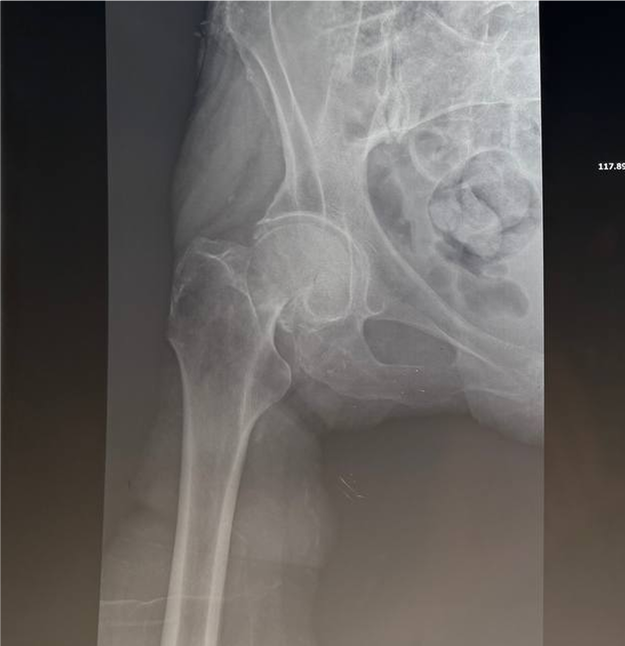

Нещодавно в лікарні було проведено ендопротезування жінці 80 років. Операція пройшла успішно — пацієнтка почувається добре та вже розпочинає етап реабілітації. 💙